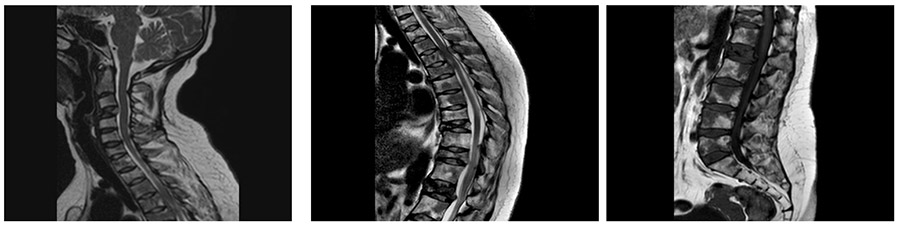

Before the surgery: MRI shows compression fractures and spinal cord compression in the upper back region, accompanied by a risk of fracture.